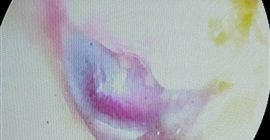

في إنجاز طبي جديد يضاف إلى سجل النجاحات الطبية لجامعة سوهاج، نجح فريق طبي بقسم الأنف والأذن والحنجرة بمستشفى سوهاج الجامعي في إجراء عملية دقيقة ونادرة لاستئصال ورم وعائي دموي بالأذن الوسطى (Glomus Tympanicum) لمريضة تبلغ من العمر ٤٧ عامًا من محافظة قنا، وذلك بإستخدام منظار الأذن الوسطى، لتعد هذه العملية الأولى من نوعها التي تُجرى بهذه التقنية داخل محافظة سوهاج.

ومن جانبه، قال الدكتور مجدي القاضي، عميد كلية الطب البشري ورئيس مجلس إدارة المستشفيات الجامعية، إن العملية تمت بتقنية منظار الأذن الوسطى، وهي من التقنيات الحديثة التي تتيح رؤية دقيقة لتجويف الأذن دون الحاجة لأي جراحة خارجية، مما يقلل المضاعفات ويسرّع من فترة التعافي، مؤكدًا أن هذا الإنجاز يمثل خطوة متقدمة نحو توطين جراحات المناظير الدقيقة بالأذن في صعيد مصر.

وأشار الدكتور أحمد كمال، المدير التنفيذي للمستشفيات الجامعية، إلى أن العملية أجريت بعد سلسلة من الفحوص الدقيقة، شملت اختبارات السمع، والأشعة المقطعية والرنين المغناطيسي بالصبغة، حيث تم استئصال الورم بالكامل تحت التخدير الكلي باستخدام المنظار، مع الحفاظ على عظيمات الأذن والعصب الوجهي وشرايين المخ المجاورة، وهو ما يعكس الكفاءة العالية للفريق الطبي.

وفي السياق ذاته، أوضح الدكتور محمد عبد الغفار، رئيس قسم الأنف والأذن والحنجرة، أن هذه الجراحة تعد إنجازًا نوعيًا للقسم، حيث تمت من خلال قناة الأذن الخارجية دون أي شق جراحي، باستخدام منظار الأذن الوسطى، الذي أتاح التعامل الدقيق مع الورم واستئصاله بالكامل مع الحفاظ على طبلة الأذن بحالتها الطبيعية، مؤكداً استمرار القسم في إجراء مثل هذه العمليات الدقيقة لخدمة مرضى سوهاج ومحافظات الصعيد